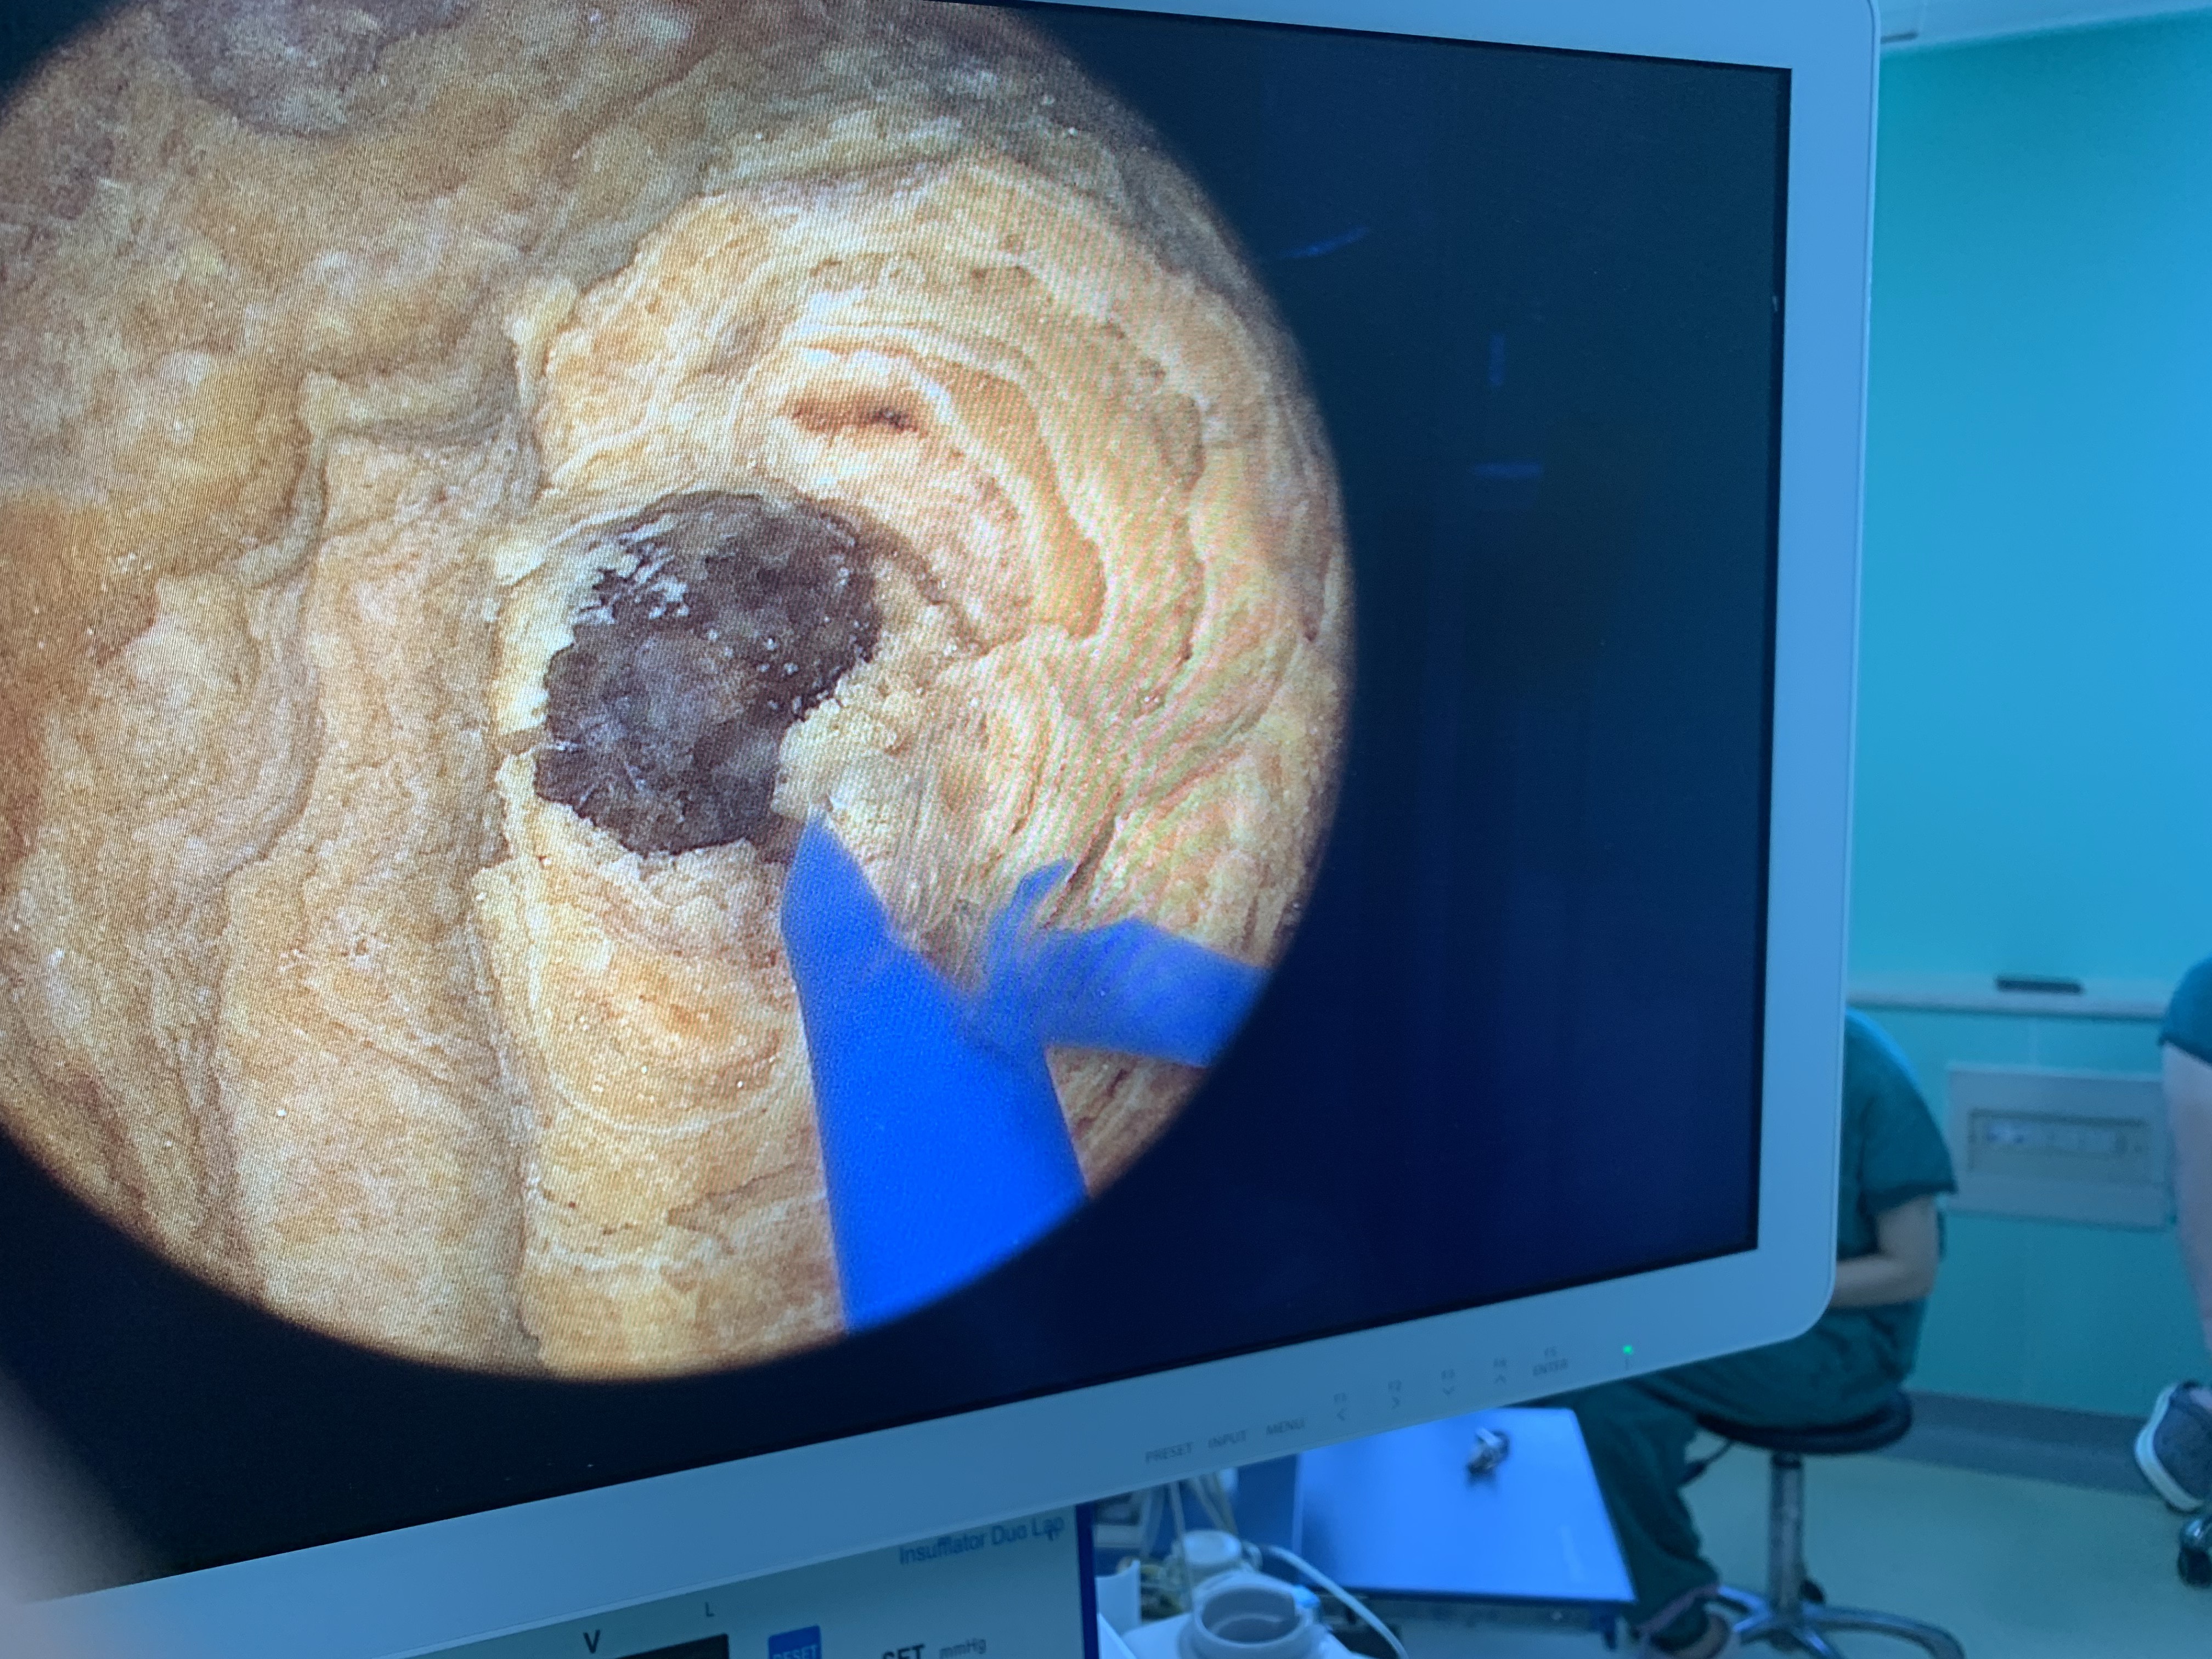

膀胱大结石一朝解除

患者男性,79岁,近期出现血尿,同时伴有尿频,尿急,偶有尿痛。患者来院就诊。经完善泌尿系ct检查:如下膀胱内大结石,直径约5cm。若按照以前方案,手术需采取下腹纵形切口,开放切开取石。这种方法,随可以一次性取出结石,但术后可能会出现伤口漏尿,感染可能,同时下腹会留下很长的手术瘢痕。我们采取微创的经尿道肾镜下EMS碎石,边碎石边吸出碎石渣,提高手术效率,一次性解决95%以上的结石。对患者创伤达到最小,同时患者恢复很快。术后复查CT如下:目前泌尿系结石治疗已经进入微创治疗时代,逐渐摈弃开放手术。为患者带来最大的受益。